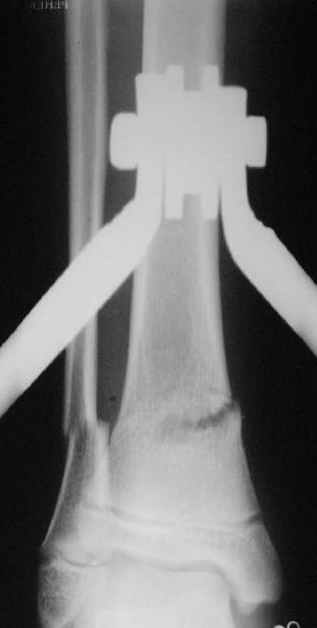

Фиксация

|